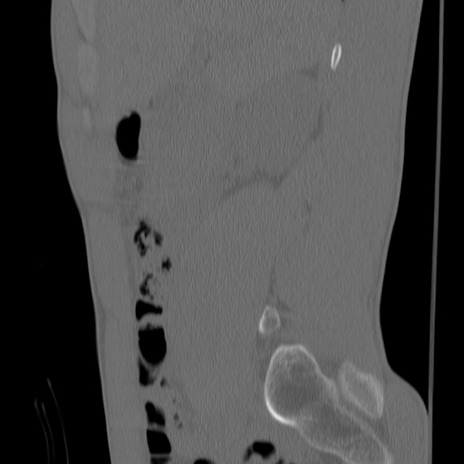

症例3 腰椎CT(矢状断像)

腰椎CT

冠状断像